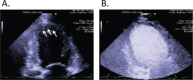

Echocardiography has evolved over the past 45 years from a simple M-mode tracing to an array of technologies that include two-dimensional imaging, pulsed and continuous wave spectral Doppler, color flow and tissue Doppler, and transesophageal echocardiography. Together, these modalities provide a comprehensive anatomic and functional evaluation of cardiac chambers and valves, pericardium, and ascending and descending aorta. The switch from analog to digital signal processing revolutionized the field of ultrasound, resulting in improved image resolution, smaller instrumentation that allows bedside evaluation and diagnosis of patients, and digital image storage for more accurate quantification and comparison with previous studies. It also opened the door for new advances such as harmonic imaging, automated border detection and quantification, 3-dimensional imaging, and speckle tracking. This article offers an overview of some newer developments in echocardiography and their promising applications.